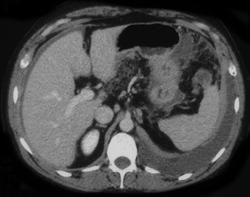

女,68y,下腹疼3月,一月半前院外ct示上腹未见异常。近1月来,症状加重。4天前入院,b超示胸腹水。今日呕吐频繁。  生化检查:  结核抗体阴性,血沉18mm/h, 癌胚抗原阴性,胸水细胞学检查见多数淋巴细胞。 白细胞总数5.4x10^12/l,血红蛋白104g/l.

患者右中腹部肠管聚集,内密度不均,可见片絮状及结节样增密影,小肠壁增厚,与之相邻处有软组织影。

1)右侧腹腔前部见类似“网膜饼”样改变,考虑网膜转移瘤。2)腹水。

腹膜污染[大网膜增厚可见污垢征及小班结与饼片影,肠系膜增厚],大量腹水。考虑癌性腹膜炎,建议查腹水。结核待排.注意上腹部及胃肠道检查